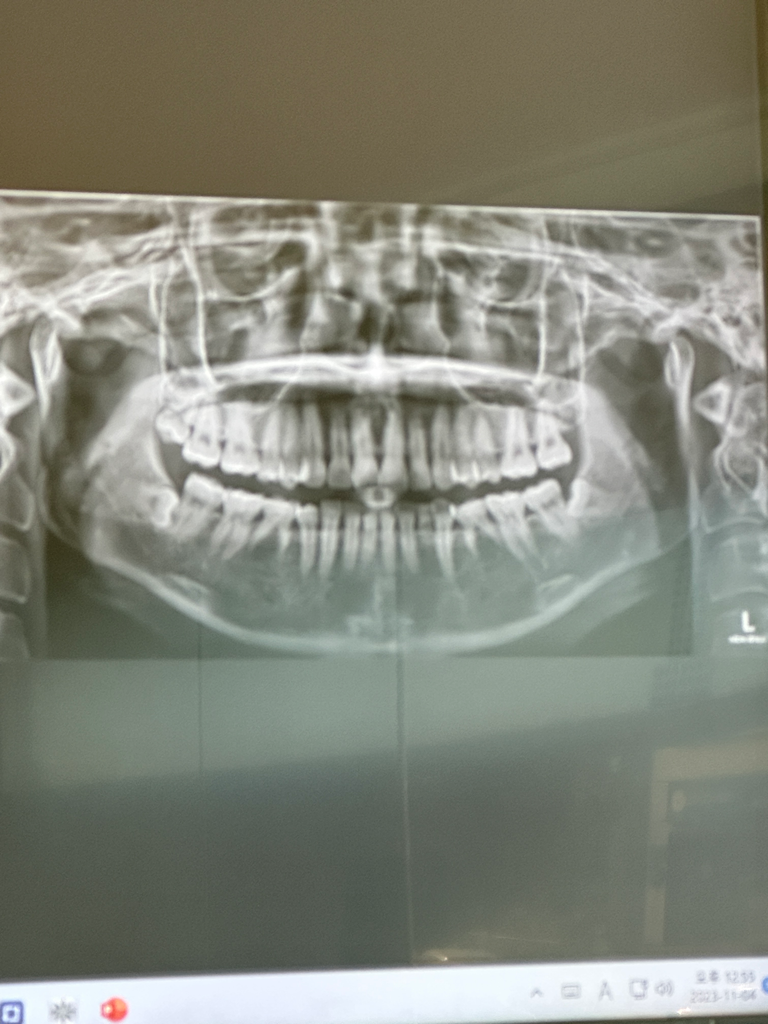

영구치 결손 치아 교정 방법 결정

하악에 영구치 3개가 없는 상태이며 현재 유치로 버티고 있는 중입니다(32세)

• 1번 째 사진